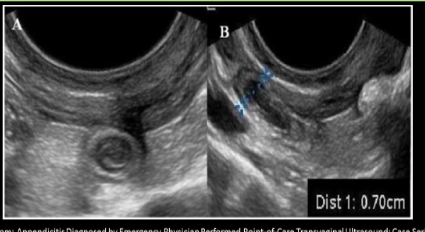

USA acute appendicitis

Use graded compression technique

Blind ended structure that will not respond to compression

Aperistalic tube with gut signature that arises from cecum base

TARGET SIGN trans

INCREASED vascularity

Fluid

Gangrenous = lack of blood flow

Diameter of acute appendicitis >__, wall >__

6; 2

Appendicitis